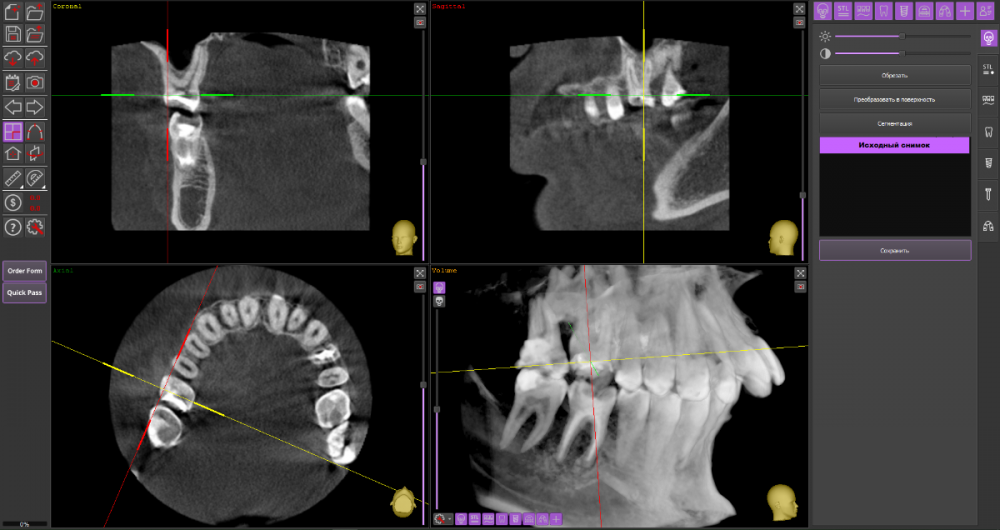

Добрый вечер, уважаемые специалисты. Подскажите, пожалуйста, есть ли возможность избежать удаления верхней 6-ки справа и использовать культевую вкладку + коронку для протезирования? Заранее спасибо за ответы. КТ: https://drive.google.com/drive/folders/17DOY2HNbp9x-5vxpit8V9hBL8D88hrAt?usp=sharing

На мой взгляд, зуб 16 вполне можно сохранить при условии адекватного лечения корневых каналов.

А вот зуб 17 перелечить маловероятно.

17_2.thumb.png.2fa36929c7852c43bbaa46a856a21963.png17_1.thumb.png.8396df0ce51d9d8d708b542619e86957.png

Я бы провел ревизию обоих зубов и далее уже смотрел что модно сохранить

после грамотной ревизии, как правило, не остаётся вопросов